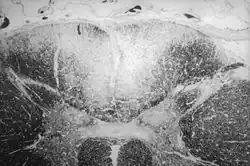

The parenchymal syphilis, present late in neurosyphilis as tabes dorsalis and general paresis. Tabes dorsalis thought to be due to irreversible loss of myelin in nerve fibers of the posterior columns of the spinal cord involving the lumbosacral and lower thoracic levels.[6] General paresis is caused by chronic inflammation of meninges and brain, leading to fibrosis of the meninges, atrophy of the cerebral cortex, and the formation of demyelinating plaques, particularly in the frontal and parietal lobes.[6] Rarely, T. pallidum may invade any structures of the eye (such as cornea, anterior chamber, vitreous and choroid, and optic nerve) and cause local inflammation and edema.[24]